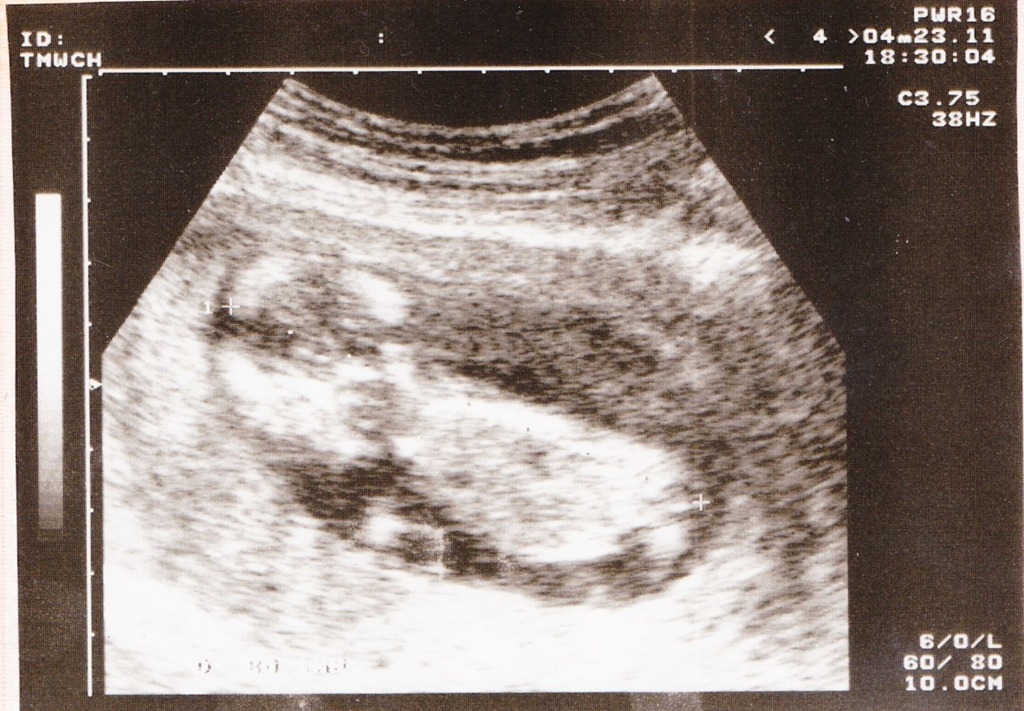

100/4/9:

12周大,已經可以在媽媽肚子裡看到我長成人形的樣子,有頭有手有腳~